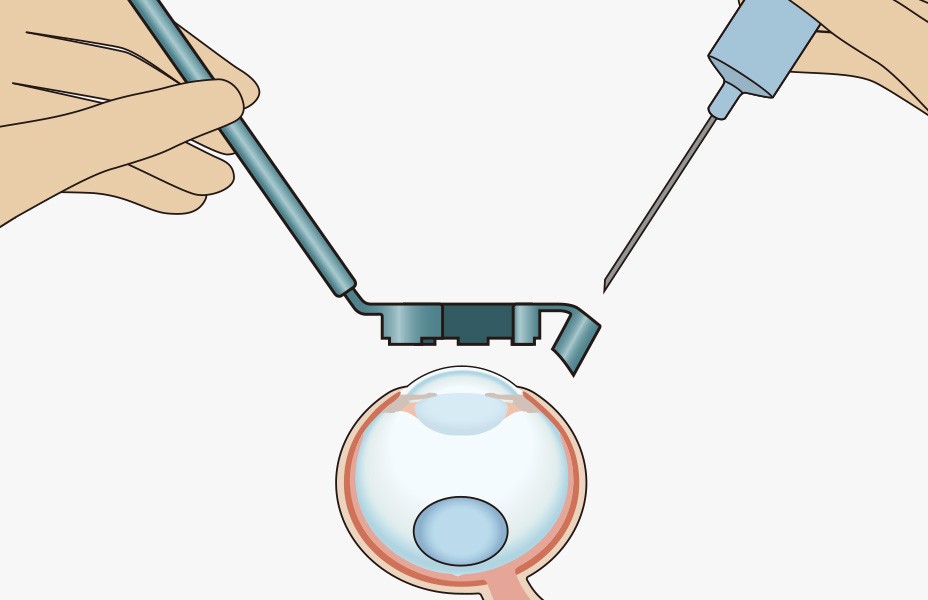

手順5:注射針抜去

■注射ガイドで強く圧迫し続けると硝子体が脱出することがあります。